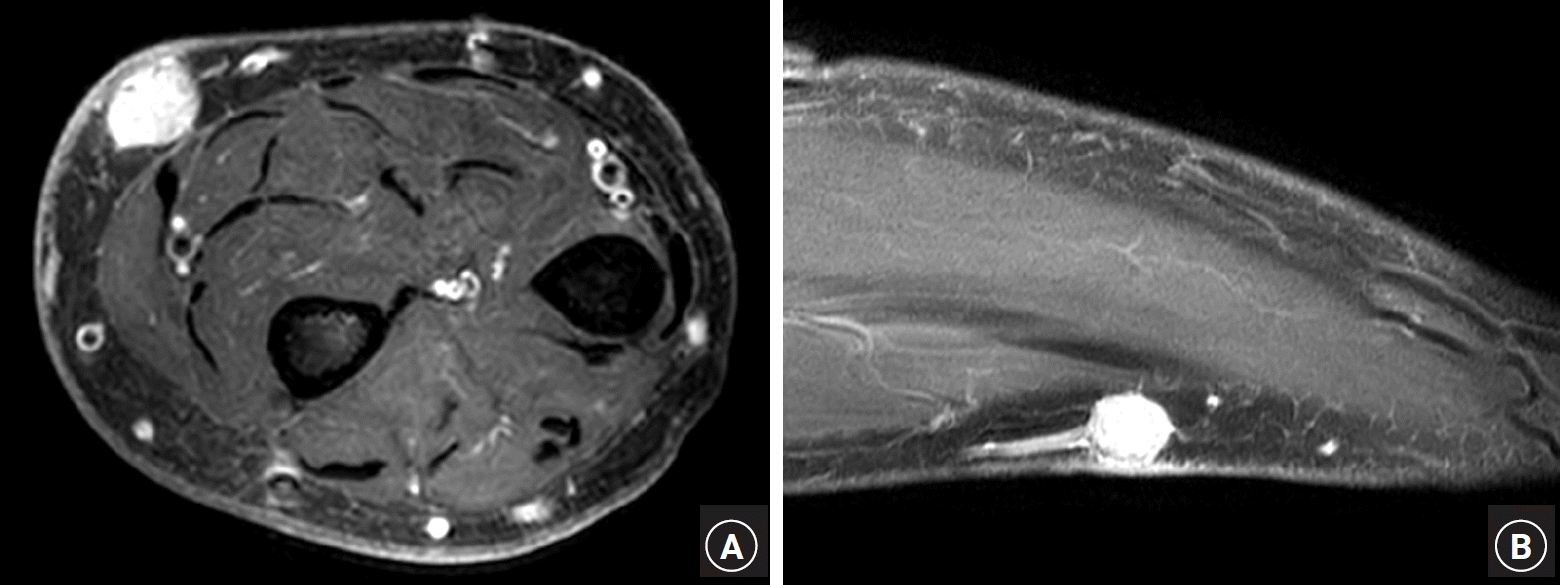

A 76-year-old man presented to our clinic with a painful, long-standing subcutaneous lump on his left forearm. The lesion, first noticed over two decades ago as an asymptomatic, tiny bump, had gradually enlarged over time. The patient had experienced increasingly frequent paroxysmal pain for the past 3 years, and the lump had become sensitive to touch. During the evaluation, the patient exhibited significant protectiveness over the affected area and flinched upon contact. Upon physical examination, a 1.2-cm movable, tender subcutaneous nodule was identified on the ulnovolar aspect of the patient’s left forearm, with brownish discoloration of its overlying skin (Fig. 1A). Preoperative magnetic resonance imaging (MRI) revealed a 1.2 × 1.1 × 0.9-cm subcutaneous mass in the anterior forearm with low T1-weighted signal intensity that avidly enhanced with contrast and high-intensity signal on T2-weighted imaging (Fig. 2).

Under general anesthesia, the lesion was explored carefully, revealing a bluish-red, round-shaped tumor with tubular structures extending from both ends (Fig. 1B). Given the uncertainties of the tubular structures, we considered that intraoperative confirmation of the tumor’s origin was necessary for definitive treatment. Although typical nerve appearances, including fascicles, were not observed, the lesion was not resected immediately; instead, the intracapsular lesion was enucleated by longitudinally splitting the tumor capsule, which was then sent for frozen section pathology. A well-demarcated, brownish lesion was easily separated from the inner capsule wall, save for a small adherent segment. The frozen section pathology suggested the lesion to be a GT. The remaining tumor capsule was also excised and submitted for permanent section pathology. The surgical wound was closed primarily after inserting a small silastic drain.

Microscopic examination revealed an encapsulated tumor comprising solid sheets of blue cells, which consisted of round glomus cells with increased vascular spaces (Fig. 3A, 3B). The neoplastic cells were positive for smooth muscle actin immunostaining (Fig. 3C). Sectional views of the tubular structure attached to the tumor revealed the presence of a blood vessel (Fig. 4A, 4B). Notably, a compressed luminal space, positive for the vascular marker CD31, was identified on the tumor’s undersurface (Fig. 4C), indicating a potential connection between the blood vessel of the tumor’s undersurface and the tubular structures (Fig. 1C). These histopathological features suggested that the GT had exerted chronic pressure on the underlying blood vessels, resulting in firm adherence of the vessel to the tumor. Postoperative recovery was uneventful, and the paroxysmal pain resolved immediately following surgery. The patient reported excellent postoperative outcomes at the 3-month follow-up with no observed complications.

Fig. 1.

Clinical and operative features. (A) A 1.2-cm subcutaneous nodule on the ulnovolar aspect of the left forearm (arrow). (B) A bluish-red, round-shaped tumor with tubular structures extending from both ends. (C) A lateral aspect of the resected lesion showing a tubular structure (white arrows) attached to the tumor’s undersurface and connected to both stalks (yellow arrows).